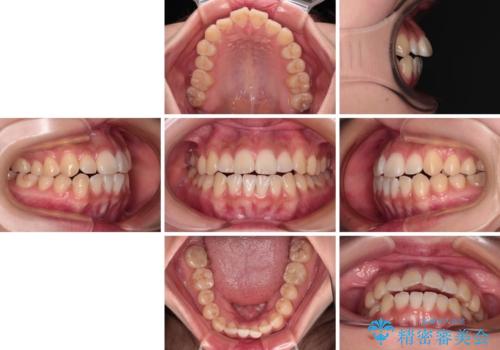

- 口元の突出感と上下前歯のズレを気にして来院された患者様です。

舌の突出癖により上下の前歯は非接触となっている状態でした。

舌のトレーニングを行わないと上下前歯の接触達成は困難であるため、トレーニングをしっかりと行っていただきながら、治療を進めて行くこととしました。

上下左右の第一小臼歯4本を抜歯し、ワイヤー装置にて矯正治療を行うこととしました。